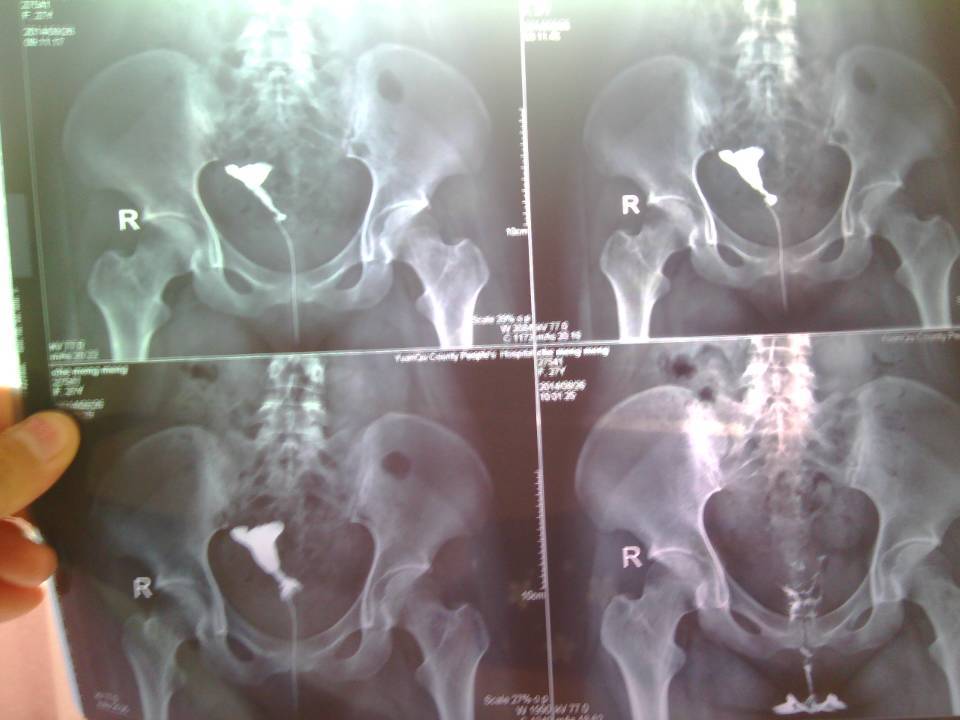

没有生过孩子,也没有流产史 就是前段时间腹部难受,做造影显示输卵管不通 很想要宝宝 这边医生建议做腹腔镜 点击展开 匿名用户 2014-08-27 10:07 为您推荐: 其他回答 你现在的情况,建议在月经干净3-7天以后,去医院做腹腔镜微创手术治疗是比较好的。 幸福的音符乐园 2014-08-28 07:10 相关问题 输卵管造影后下腹部疼,有知道原因的姐妹吗 做输卵管造影后能吃水果吗?比如红提和鲜枣?我吃后感觉腹部和宫颈有痛的现象 盆腔造影剂弥散一般,右侧输卵管通畅,壶腹部排空不良,这说明什么?